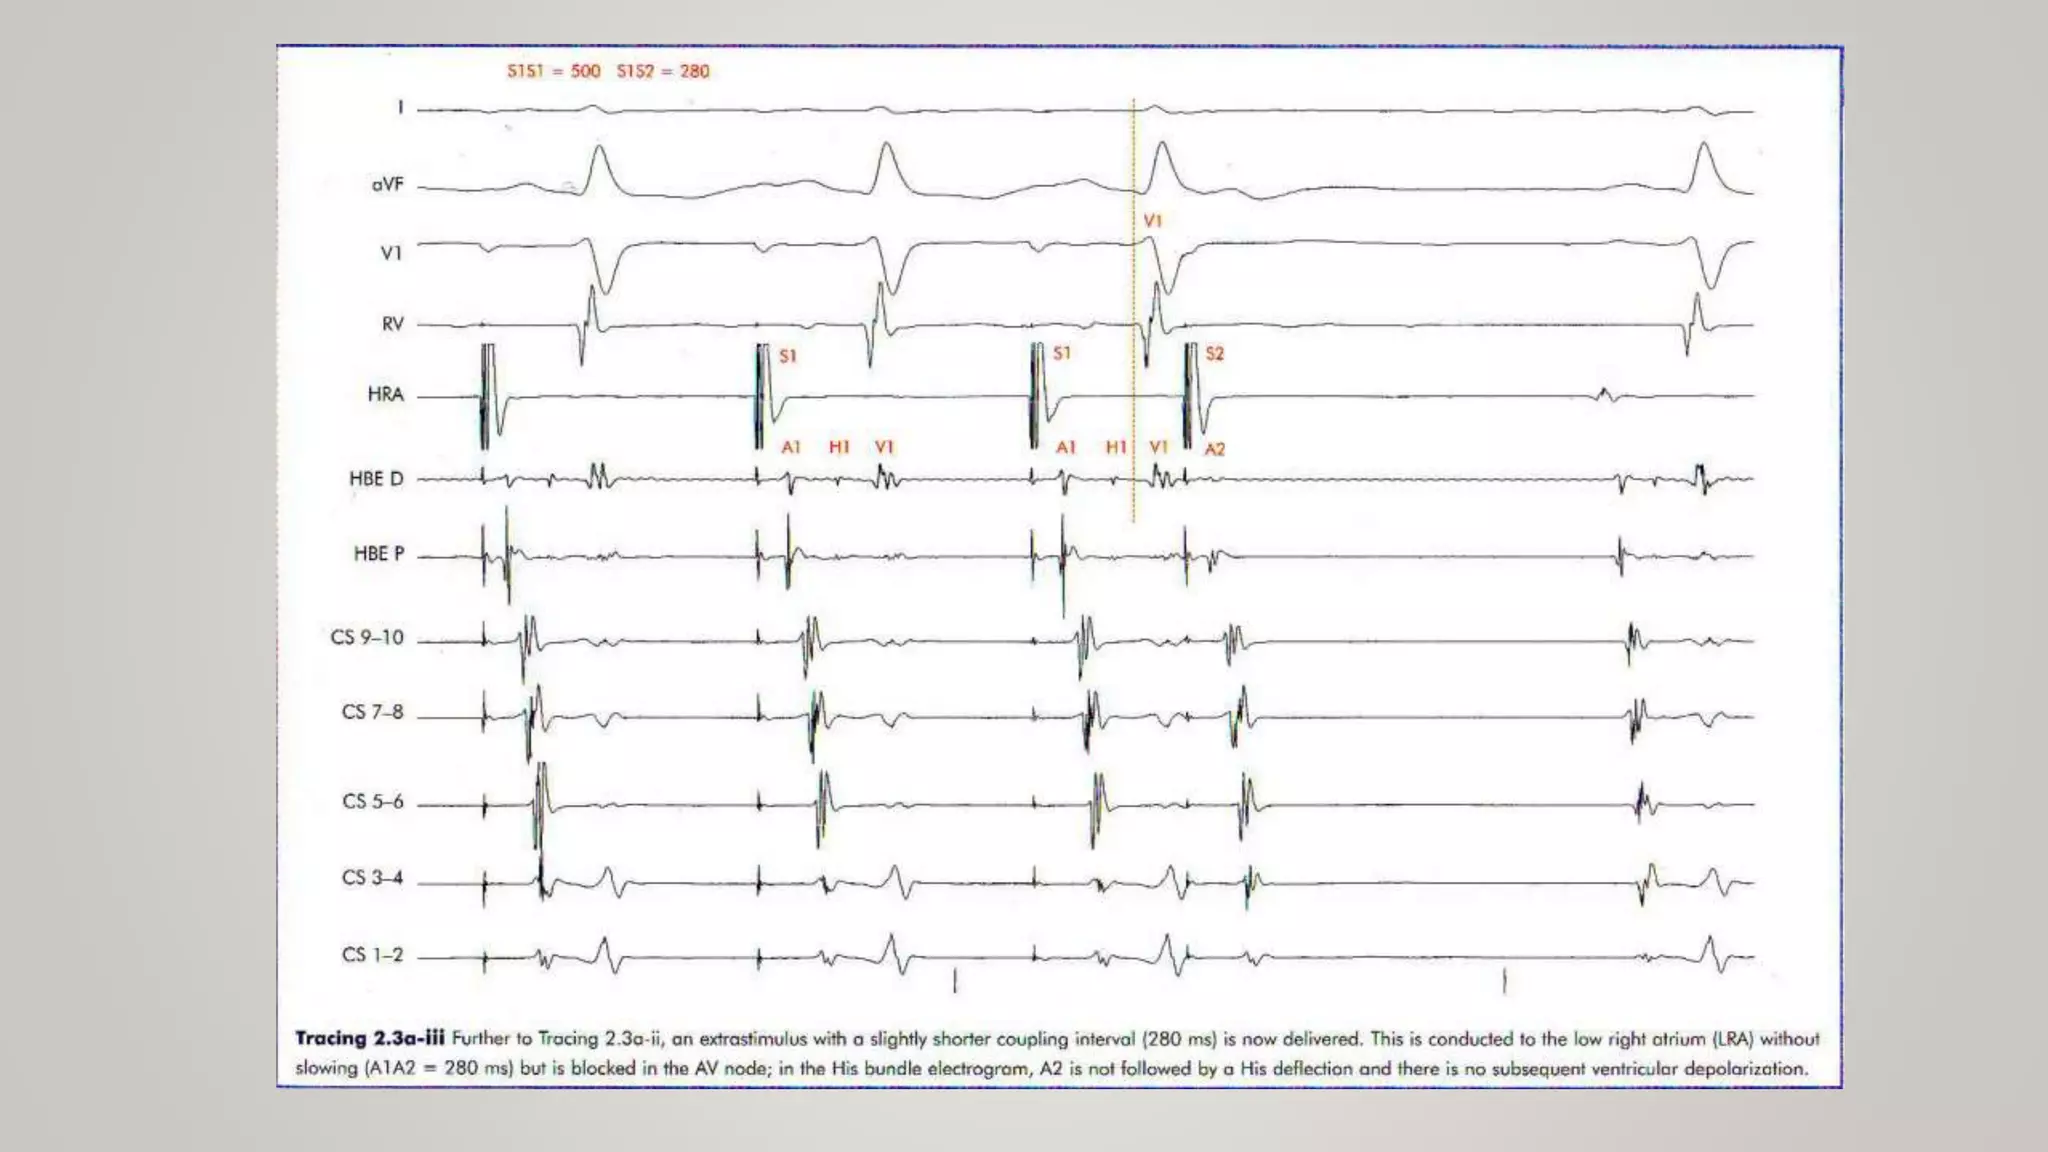

- AVNERP is the longest A1A2 interval that fails to be conducted to the His bundle.

Measurement of RefractoryPeriod • ERP : The longest coupling interval that failing to capture the tissue or the conducted over the structure. • FRP : The shortest coupling interval that can be elicited from a tissue or structure any “input” interval. • RRP : The ” input” interval to a tissue or structure at which the “output” interval just begins to differ from the “input” interval Ex. - AVNERP is the longest A1A2 interval that fails to be conducted to the His bundle. - AVNFRP is the shortest H1H2 interval that can be elicited by any A1A2 interval. - AVNRRP is the longest A1A2 interval at which A2H2 exceeds A1H1 (or H1H2 exceeds A1A2)